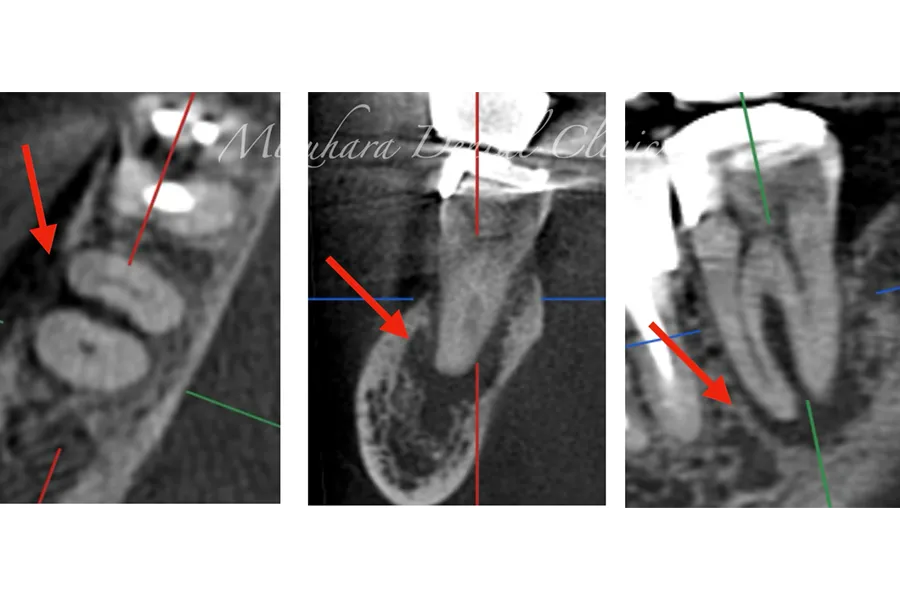

予知性の高い治療を提供できるだけ患者様の大切な歯を残し、10年、20年先まで健康な状態を保てるよう、長期的な視点で治療を計画します。そのために最も重要なのが、「診査」と「診断」です。的確な診断は精密な診査から生まれ、治療結果を大きく左右します。問診や簡易検査だけでは見逃されがちな病変も、CTやマイクロスコープなどの最新の医療機器を活用し、時間をかけて丁寧に「診査・診断」を行います。

世界基準の成功率を目指した精密根管治療

根管治療

当院では豊マイクロスコープ、ラバーダムを使用し、世界基準の成功率を目指した精密根管治療による「歯を残す」ための治療をご提供します。